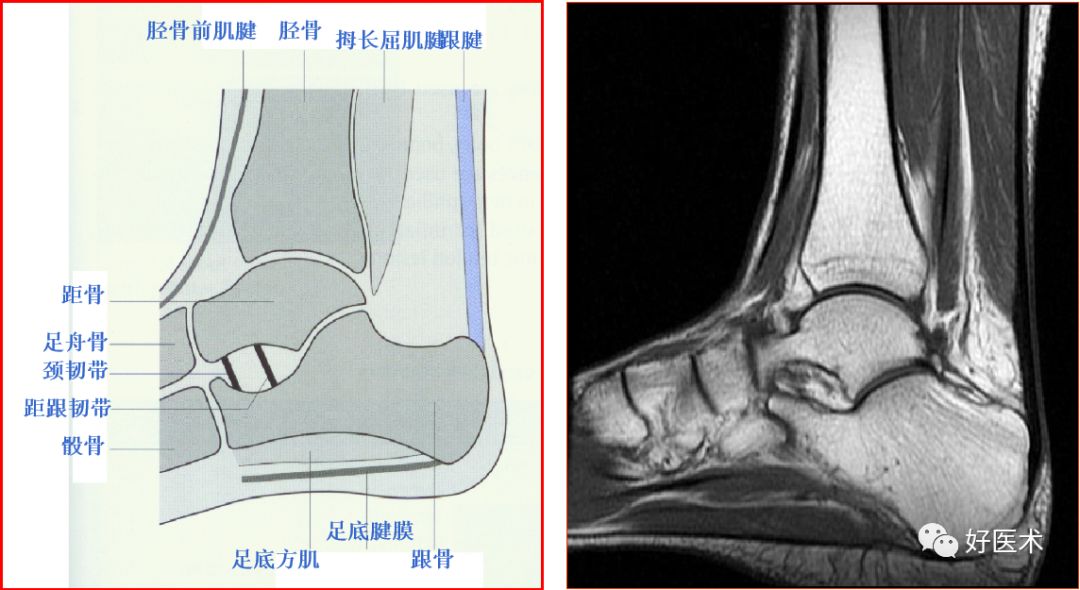

一、解剖和扫描方法

踝关节的韧带

距跟韧带